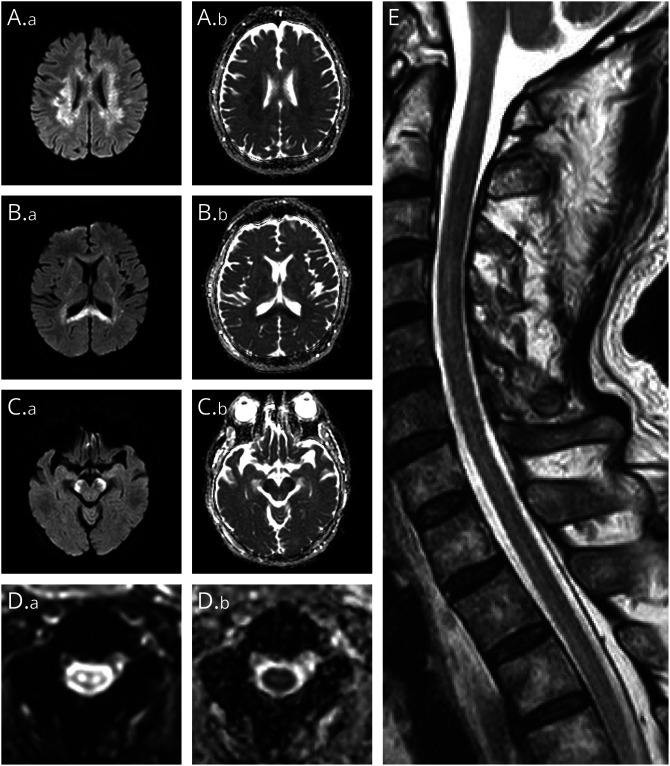

自身免疫性胶质纤维酸性蛋白星形细胞病患者的广泛皮质脊髓束受累

Extensive Corticospinal Tract Involvement in a Patient With Autoimmune Glial Fibrillary Acidic Protein Astrocytopathy.